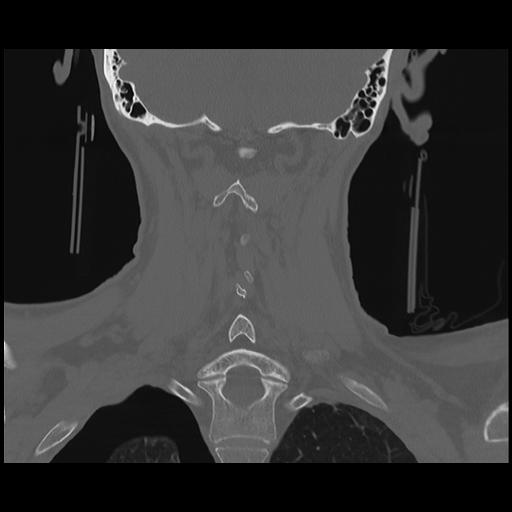

16 HUESO,,Coronal,2.000,HUESO,Coronal,